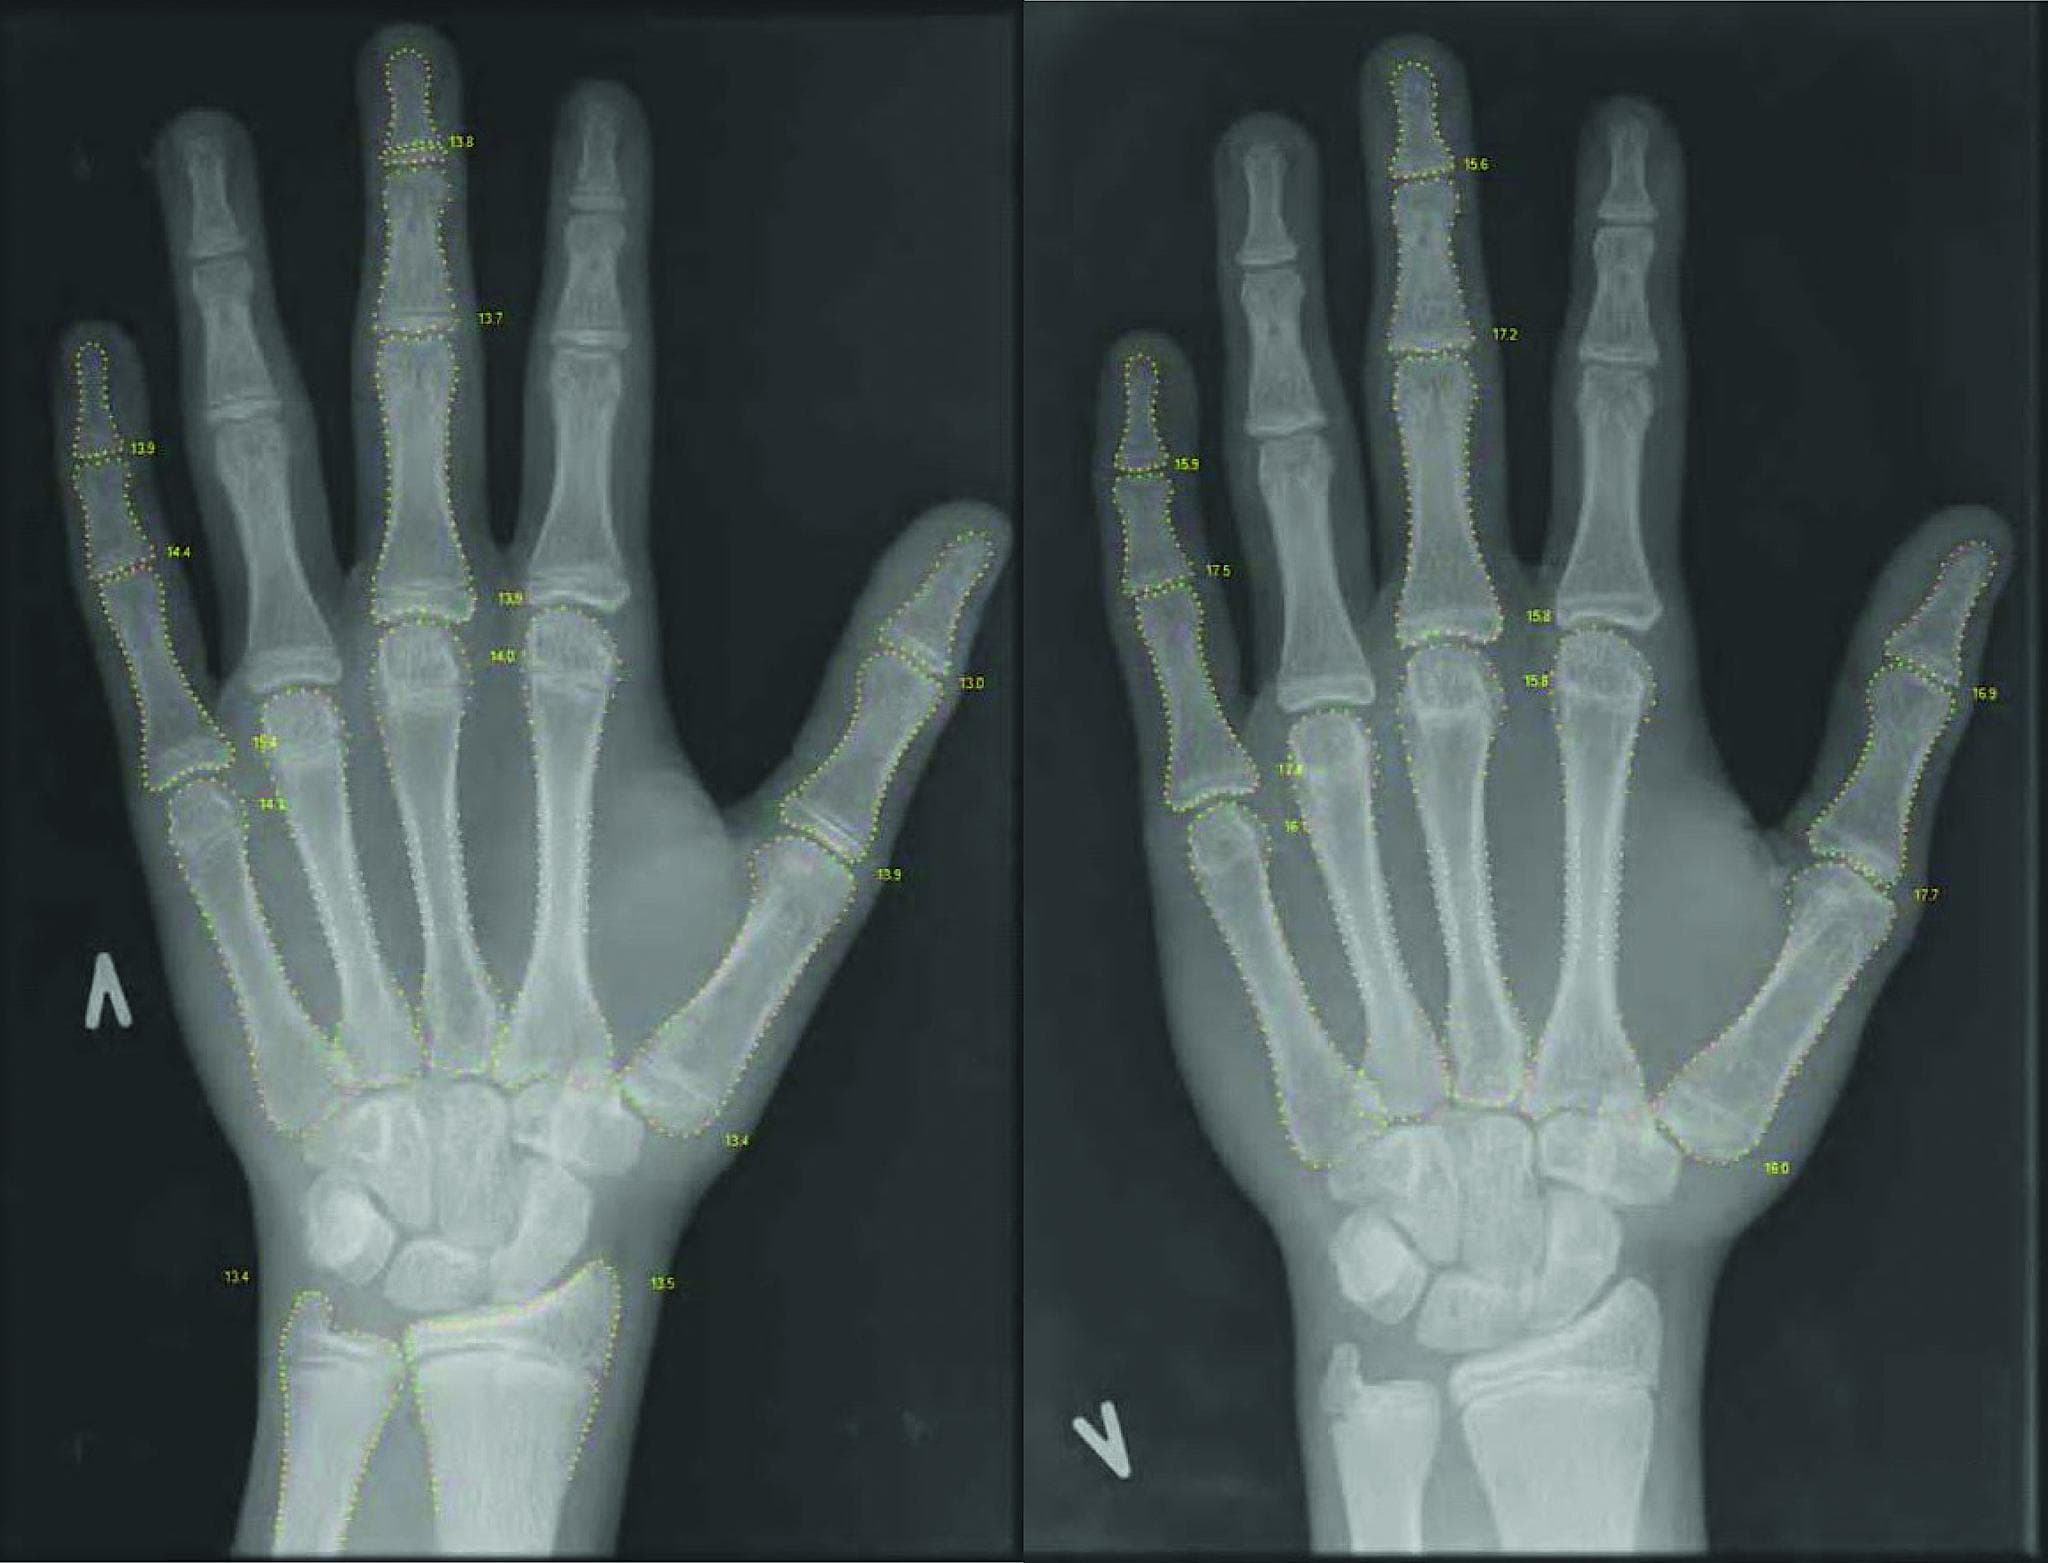

calcium total 1,37 mmol/l (referenceværdi: 2,15-2,7 mmol/l). P-basisk fosfataseniveau var 653 E/l (referenceværdi: 100-400 E/l), P-fosfatniveau var 1,52 mmol/l (referenceværdi: 1,16-1,81 mmol/l), P-parathyroideahormonniveau var svært forhøjet til 37,7 pmol/l (1,1-6,9 pmol/l) og spoturincalcium/kreatinin-ratio (Uca/cr) var meget lav 0,008 mmol/mmol (referenceværdi: 0,04-0,7 mmol/mmol). En røntgenoptagelse af hånden var uden tegn på rakitis, men bone health index (BHI) var nedsat [4] (Figur 1). Drengen var pubertetsmæssigt udviklet sv.t. Tannerstadium 4. Behandlingen indledtes med 50 mikrogram cholecalciferol og 2 g calcium dagligt. Efterfølgende svar på undersøgelse af D-vitaminmetabolitter viste svært nedsat S-25-hydroxyvitamin D (25(OH)D)-niveau til 9 nmol/l (referenceværdi 50-160 nmol/l), hvilket bekræftede mistanken om svær D-vitaminmangel, hvorimod S-1,25-dihydroxyvitamin D på 152 pmol/l (referenceværdi 51-177 pmol/l) var højt i normalområdet. Ved kontrol efter to måneders behandling med kalk og D-vitamin var calciumstofskiftet normaliseret, mens Uca/cr-niveauet fortsat var meget lavt på 0,006 mmol/mmol. Drengen beskrev betydeligt øget muskelkraft, bensmerterne var aftaget, og ledsmerterne var forsvundet. Endvidere var humøret bedre og trætheden mindre udtalt. Først efter et år var generne i form af bensmerter og træthed helt forsvundet. Desuden blev han tiltagende mere udadvendt og påbegyndte en rivende social udvikling.

Svær D-vitaminmangel hos teenagere er ofte uden kliniske tegn på rakitis, og symptomerne er ukarakteristiske, hvilket kan forsinke diagnosen [1]. Specielt forekommer symptomatisk D-vitaminmangel i perioder med høj væksthastighed pga. øget behov for calcium til knoglemineraliseringen [1]. Patienten i sygehistorien havde bensmerter og smerter i hele kroppen i to år forud for krampeanfaldet. Ved indlæggelsen var han i slutningen af puberteten og således i en fase med høj væksthastighed. Med insufficient D-vitamintilførsel vil sommerens D-vitamindepot være opbrugt i februar-marts [5], hvor hans hypokalcæmiske kramper begyndte. Trods to års anamnese med formodet svær D-vitaminmangel afslørede røntgenbilledet ingen tegn på rakitis, hvorimod BHI var nedsat som tegn på udtynding af cortex [4]. Den gradvise udvikling af svær D-vitaminmangel var måske en medvirkende faktor til social isolation. Drengens sygdom kunne formentlig have været forebygget ved at følge Sundhedsstyrelsens anbefaling om D-vitaminprofylakse til personer, der opholder sig meget indendørs.

Sygehistorien illustrerer vigtigheden af at måle S-calciumniveau ved afebrile kramper og at måle S-25(OH)D ved udredning af uforklarede ben/muskelsmerter hos teenagere. BHI bør anvendes som supplerende vurdering af røntgenoptagelser af hånden ved mistanke om D-vitaminmangel.